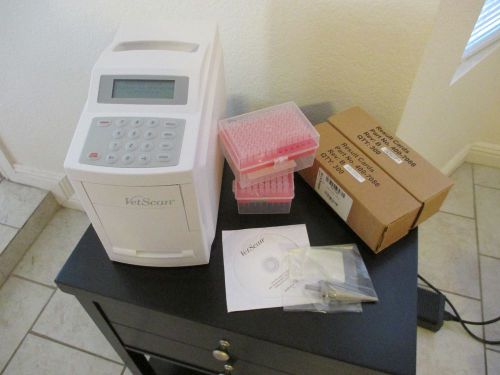

ABAXIS VETSCAN HM5 VETERINARY HEMATOLOGY BLOOD ANALYZER CBC RBC

ABAXIS VETSCAN VS2 VETERINARY BLOOD CHEMISTRY ANALYZER